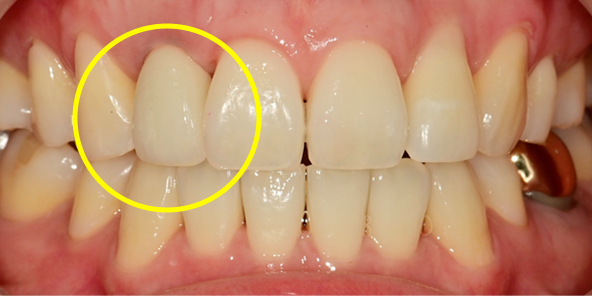

Final Implant Results

BEFORE/AFTER

BEFORE

AFTER